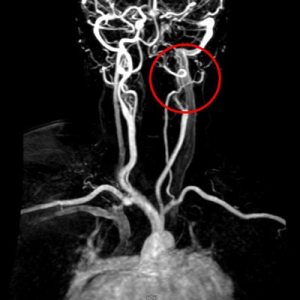

南區腦中風病人緊急送往花蓮慈院 醫療團隊把握黃金時間取栓治療

居住在花蓮南區的56歲甘女士,日前在家起床後,突然感到口齒不清、右半身無力,並有些微意識混亂,身為消防隊員的兒子十分警覺,緊急叫救護車將她送往花蓮慈濟醫院急診。救護車於上午八點抵達,經檢查確認是左側內頸動脈急性梗塞,神經外科醫療團隊立刻進行取栓手術,在病人到院後90分鐘內即完成取栓治療,目前病人恢復情況良好。